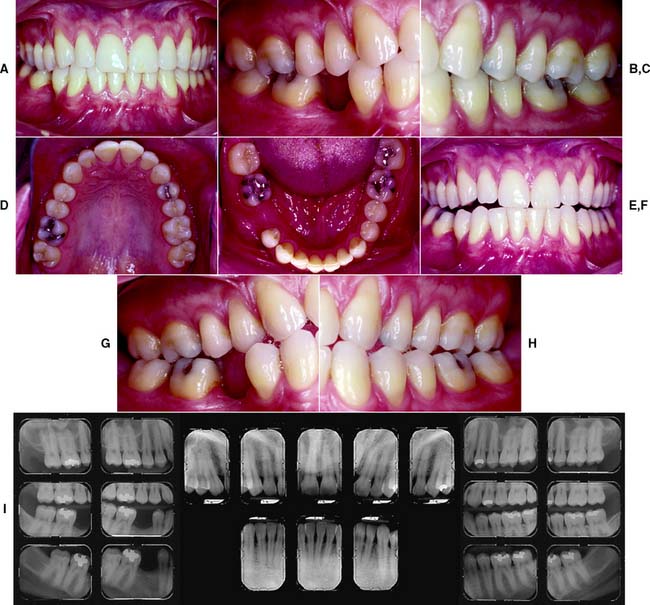

This class (Figs. 1-33 and 1-34) is characterized by severely compromised location and extent of edentulous areas with guarded prognosis, abutments requiring extensive therapy, occlusion characteristics necessitating reestablishment of the occlusion with a change in the occlusal vertical dimension, and residual ridge conditions.

Fig. 1-33 Class IV patient. Edentulous areas are found in both arches, and the physiologic abutment support is compromised. Abutment condition is severely compromised as a result of advanced attrition and failing restorations, necessitating extracoronal restorations and adjunctive therapy. The occlusion is severely compromised, necessitating reestablishment of occlusal vertical dimension and proper occlusal scheme. A, Frontal view, maximum intercuspation. B, Right lateral view, maximum intercuspation. C, Left lateral view, maximum intercuspation. D, Occlusal view, maxillary arch. E, Occlusal view, mandibular arch. F, Frontal view, protrusive relationship. G, Right lateral view, right working movement. H, Left lateral view, left working movement. I, Full-mouth radiographic series.

(From McGarry TJ, et al: Classification system for partial edentulism. J Prosthodont 11:181, 2002.)